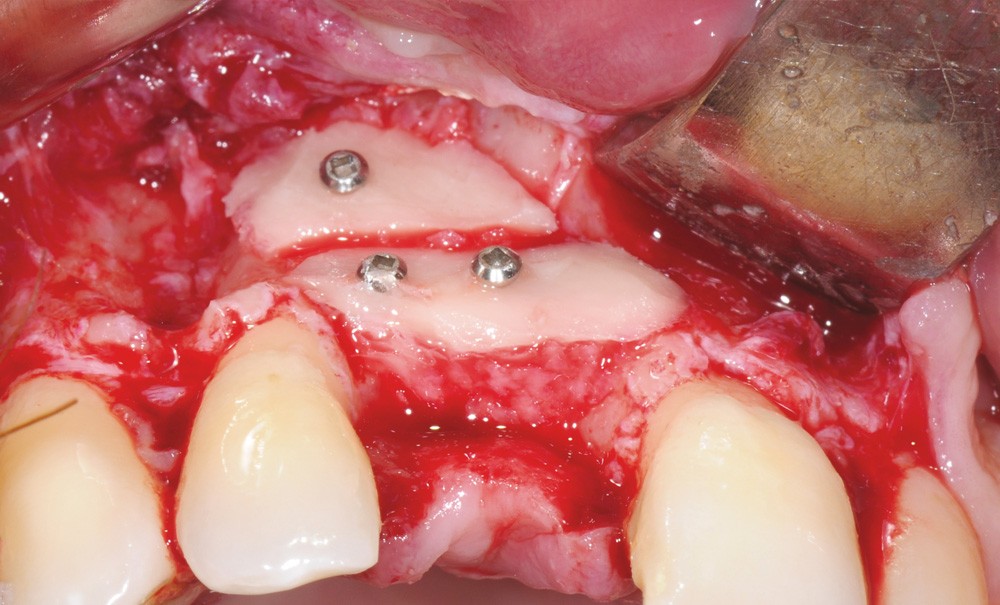

La technique de greffe autogène est basée sur la préparation des blocs corticaux mandibulaires prélevés dans la zone rétro-molaire. La forme de la nouvelle crête est reconstruite par de fines plaques corticales jouant le rôle d’une membrane biologique. Grâce à cette méthode, la transplantation de blocs mandibulaires constitue une méthode prédictible pour la régénération osseuse.

La crête reconstruite permet un positionnement idéal de l’implant dans l’os régénéré. La gestion esthétique de la restauration antérieure peut être améliorée par différentes techniques selon l’étendue du défaut. Pour une restauration unitaire, un greffon de conjonctif tubérositaire est associé à la pose de l’implant. Lorsque la réhabilitation concerne deux implants adjacents, un bloc inter-implantaire stabilisé avec une vis d’ostéosynthèse et un greffon de conjonctif dense permettent de soutenir la papille inter-implantaire. Enfin, lorsque la zone à reconstruire est étendue, le volume vestibulaire peut être augmenté lors de l’implantation avec une technique de régénération osseuse guidée.